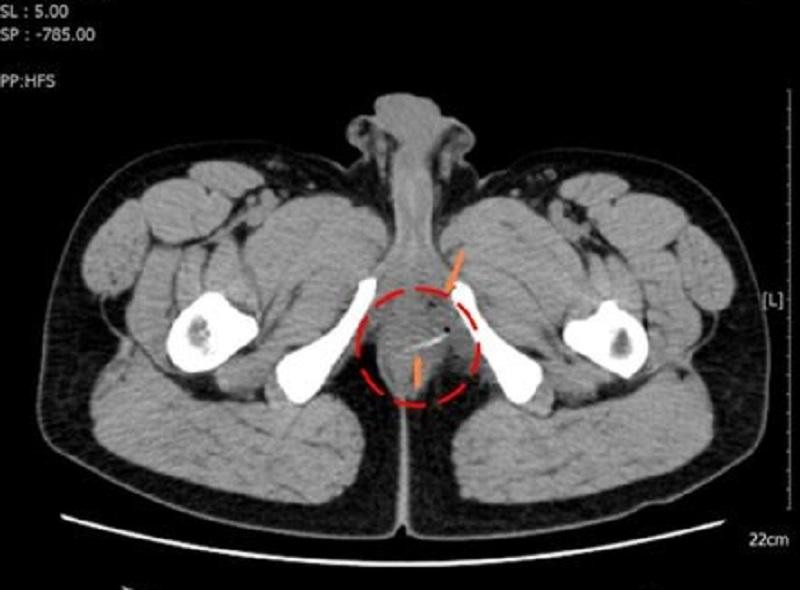

| Bệnh nhân được chụp CT-Scan truy tìm nguyên nhân gây đau bất thường ở vùng hậu môn |

Trên hình ảnh kiểm tra, bác sĩ phát hiện vùng đại tràng của bệnh nhân có dị vật cản quang hình que kèm bóng khí. Bệnh nhân đã được chỉ định nhập viện phẫu thuật.

| Hình ảnh kiểm tra phát hiện chiếc xương cá cản quang ở vị trí trực tràng của bệnh nhân |

Trong quá trình mổ, ê kíp phát hiện chiếc xương cá dài khoảng 3cm nằm ở vùng trực tràng, đâm thủng thành ruột và tạo áp xe nhưng may mắn chưa gặp biến chứng nguy hiểm. Các bác sĩ đã lấy dị vật ra khỏi cơ thể bệnh nhân và khâu lại vết thương. Sau phẫu thuật, sức khỏe của bệnh nhân đã bình phục tốt.